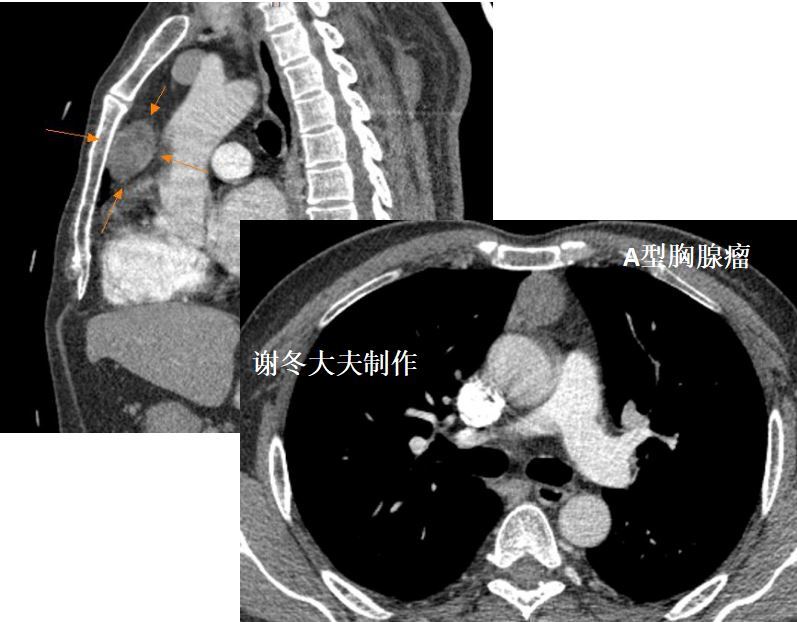

4.谢大夫,这个前纵隔占位,是胸腺瘤吗?

回答:这是一个纵隔畸胎瘤,不是胸腺瘤,这个肿瘤内部包含很多脂肪成分,以及钙化影,这些都是典型纵隔畸胎瘤的表现